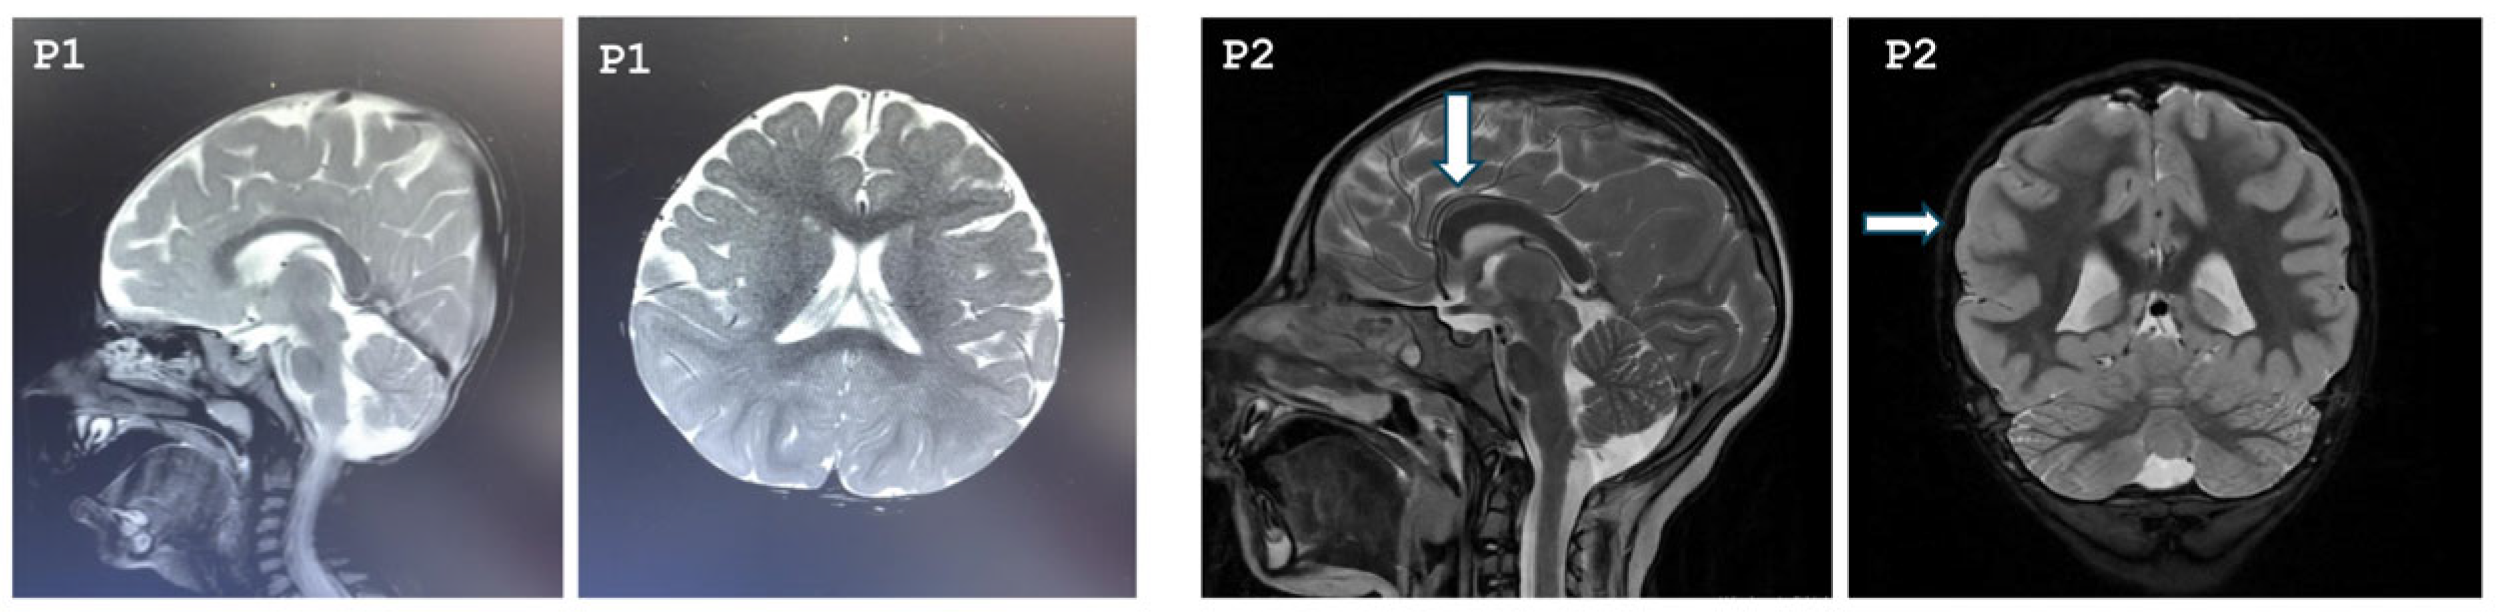

3.1. Clinical Features

3.2. Common Findings

| Cranial MRI | Diffuse parenchymal volume loss in both cerebral hemispheres | The frontal lobes appear smaller than normal in both cerebral hemispheres, hypoplastic corpus callosum, pachygyria, absence of pineal gland | Normal | Normal | Normal | Retrocerebellar arachnoid cyst | Normal |